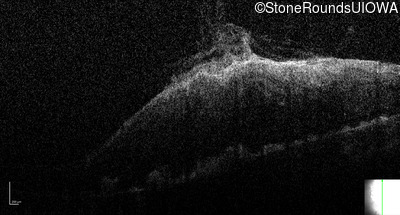

This 9 year old male was noted to have some crossing of his eyes at 2 months of age and the eye exam which followed identified a retinal lesion in the right eye. When he was six years old an epiretinal membrane was noted in his left eye. Two years later it was decided that it was a thin hamartoma in that eye as well. He underwent neuroimaging at age 7 which identified bilateral acoustic neuromas.

| Age at visit: 11 years |

| Age at visit: 14 years |